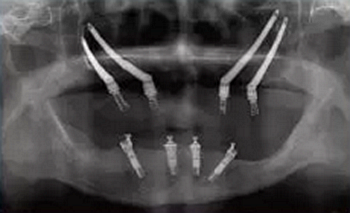

圖 3 雙顴種植體植入術(shù)后全景片

Figure 3 Radiographic of post?surgery of quad zygomatic implants placement

前牙區(qū)剩余骨量嚴(yán)重不足而無法植入常規(guī)種植體的患者, 不符合顴骨種植的經(jīng)典術(shù)式適應(yīng)癥。Bothur[16]等學(xué)者提出單側(cè)顴骨植入多枚種植體的可行性, 并分別于雙側(cè)顴骨各植入2枚和3枚種植體, 繼而提出雙側(cè)顴骨各植入2枚顴骨種植體的改良術(shù)式(zygomatic quad approach)[17, 18, 19, 20], 又稱之為雙顴種植體植入術(shù)(圖3)。該改良術(shù)式較經(jīng)典術(shù)式的適應(yīng)癥更為廣泛, 能獲得更加優(yōu)化的植體受力分布。但研究指出[21], 單側(cè)顴骨植入2枚種植體時, 更容易出現(xiàn)種植體位置過近, 傷及眼球、眶下神經(jīng)血管等重要解剖結(jié)構(gòu), 引起嚴(yán)重的手術(shù)并發(fā)癥。 為了提高顴種植體植入手術(shù)的精準(zhǔn)性和安全性, 目前臨床上有學(xué)者使用計算機輔助手術(shù)導(dǎo)航技術(shù)來幫助完成手術(shù)(圖4 ~ 5)。